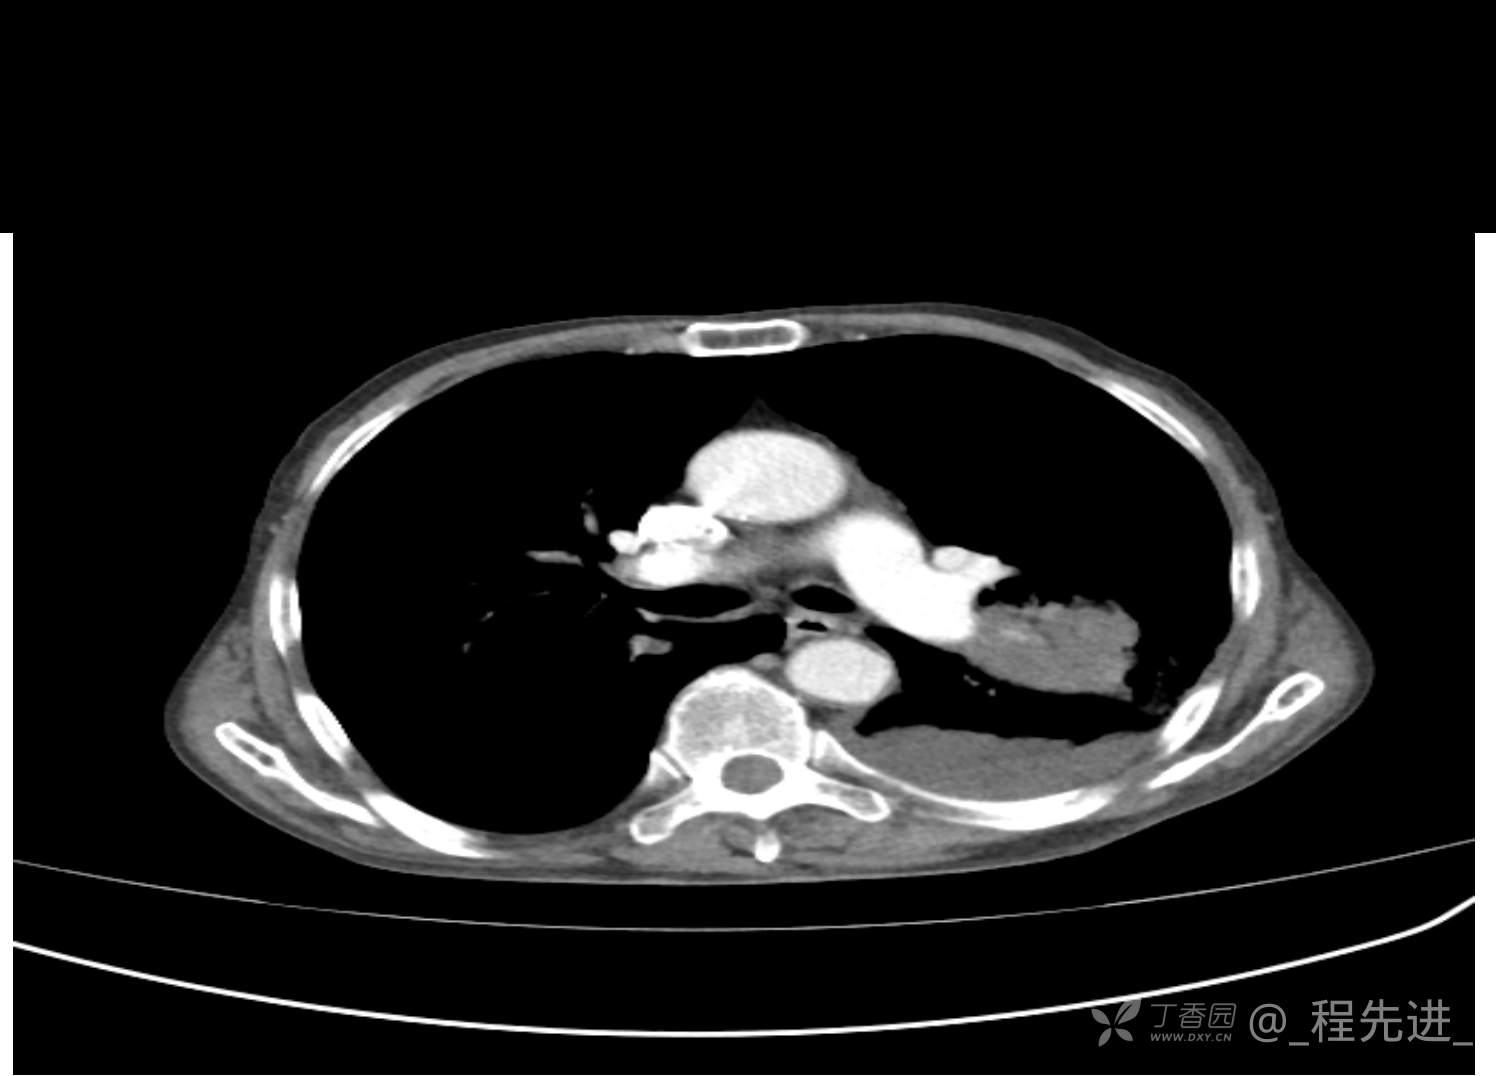

患者性别:男

患者年龄:81岁

简要病史:反复咳嗽、咳痰20余年,加重1周。两肺呼吸音低,可闻及散在干湿啰音。